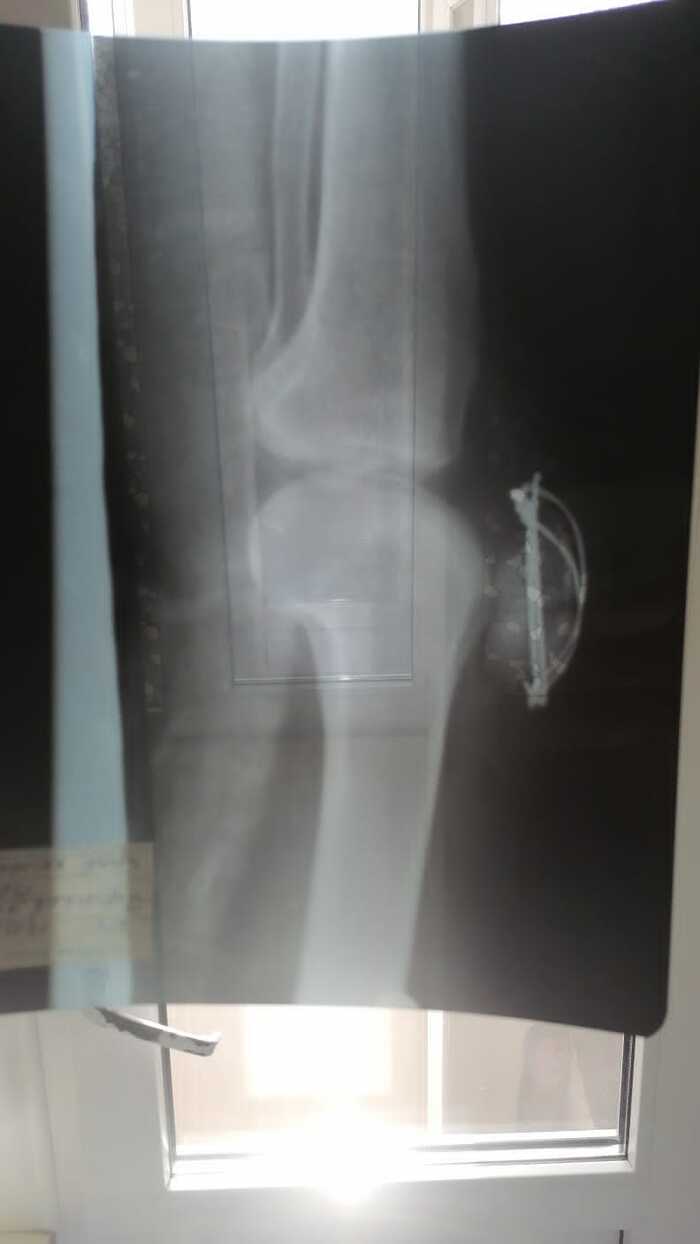

В начале марта 09.03.22 упал и в результате получил перелом надколенника. Была проведён остеосинтезе по Веберу 15.03.22. Нужна консультация в плане того когда можно давать нагрузку на ногу без сгибания в колене. От этого зависит как быстро смогу начать ходить и выйти на работу, так как на один больничный семью просто не вытяну. Информация от лечащего врача противоричивая: то можно давать нагрузку то нельзя.